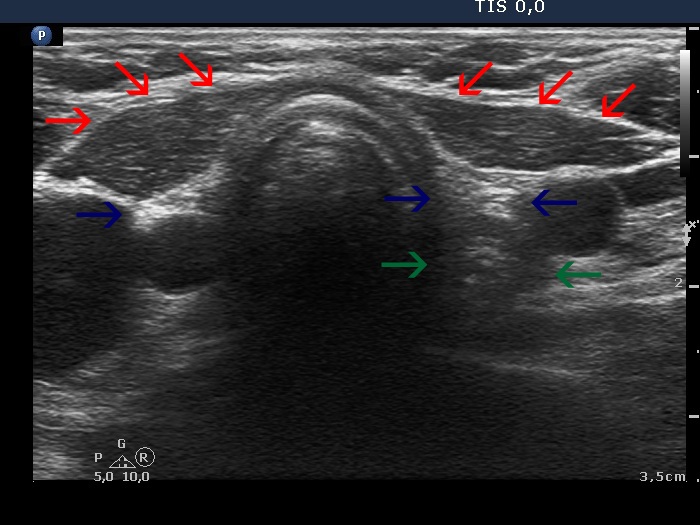

The operated thyroid - case 775 |

Clinical data: A 55-year-old woman was referred for follow-up examination. She underwent total thyroidectomy because of toxic multinodular goiter 7 years ago. She had no complaints.

Ultrasonography: There was no parenchyma according to the thyroid lobes.